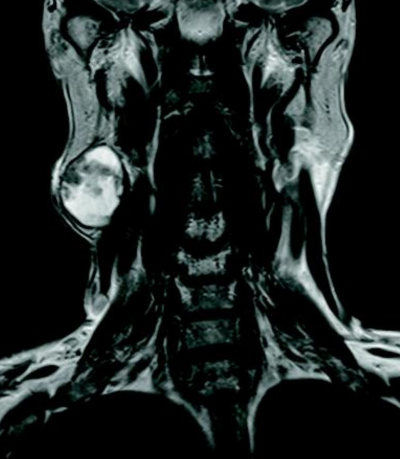

60 歳の男性。右耳下部腫瘤を主訴に来院した。1か月前、洗顔時に気付いたが痛みはなくそのままにしていたという。右耳下腺後下部に軟らかい腫瘤を触れる。穿刺吸引細胞診で囊胞性背景に胞体が好酸性の上皮細胞集塊を認める。頸部 MRIを別に示す。⁹⁹mTcO₄⁻ 唾液腺シンチグラフィで病変部に集積を認める。

T2強調像水平断像

T2強調冠状断像